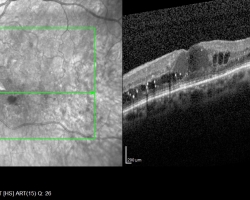

• OCT (2018)

œdème maculaire diabétique bilatéral